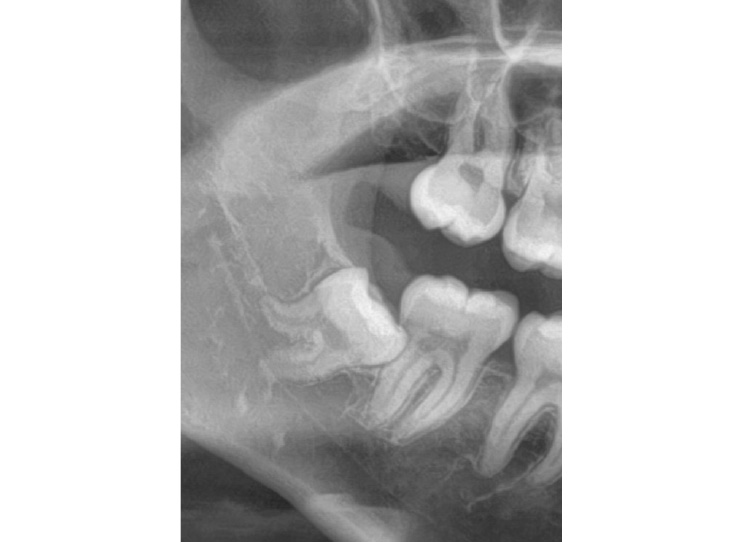

右下の奥歯が腫れて痛い、といって来院された20代男性の患者さまです。患者さま本人は、あまり親知らずを意識していなかったようですが、横向き・半分歯茎に埋まった状態の親知らずの周りの歯茎が炎症を起こしていました。初診では炎症が強かったため抜歯すべきでないと判断し、抗生物質を処方いたしました。2回目の来院の際に抜歯(所要時間:約20分)を行いました。

抜歯前

抜歯後